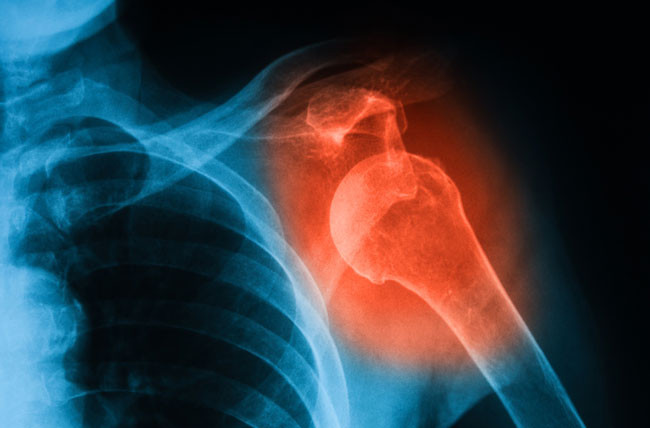

Frozen shoulder atau kapsulitis adesif adalah kondisi yang ditandai dengan kekakuan dan nyeri pada sendi bahu. Seiring waktu, bahu bisa menjadi sangat sulit digerakkan. Frozen shoulder adalah kondisi yang langka dan melibatkan penebalan serta kontraksi dari otot-otot di sekitar sendi bahu. Menurut American Academy of Orthopaedic Surgery, kondisi ini terjadi pada 2% masyarakat. Terapi fisik untuk memperbaiki fleksibilitas bahu menjadi pengobatan yang direkomendasikan pada pasien frozen shoulder.

Ada tiga tulang yang menyusun sendi bahu, yaitu tulang lengan atas, tulang belikat atau skapula, dan tulang selangka. Terdapat jaringan ikat kuat dan dikenal dengan nama kapsul bahu, yang menyelubungi sendi bahu. Cairan sendi akan melumasi sendi agar bahu dapat bergerak dengan mudah.

Pada frozen shoulder, kapsul bahu akan menebal dan kaku, membuat pergerakan bahu menjadi terbatas. Ditemukan juga penurunan cairan sendi pada banyak kasus. Namun penyebab pasti terjadinya frozen shoulder ini masih belum dipahami sepenuhnya. Diduga kondisi ini lebih mungkin terjadi pada penderita patah tulang lengan atas atau yang baru menjalani prosedur operasi, yang membuat mereka tidak menggerakkan bahu dalam waktu lama.

• X-ray

Pemeriksaan x-ray ini bisa membantu melihat bila ada perubahan pada struktur tulang di bahu seiring waktu. Pemeriksaan ini juga bisa memperlihatkan bila ada masalah lain pada bahu Anda, seperti arthritis.